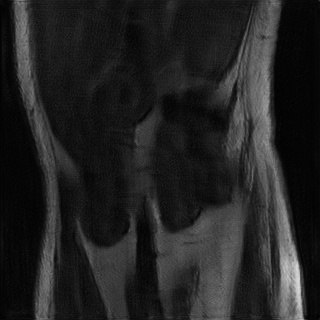

Accelerated MRI enhancement: The FastMRI [3] database consists of more than 1500 multi-coil diagnostic knee MRI scans and corresponding emulated single-coil data. Our experiments are based on a subset of nearly 800 coronal proton-density weighted scans without fat-suppression from the official train and validation single-coil releases. We remove of the patients for evaluation and split the remaining patients into input and target data. While the target domain consists of slices from fully-sampled MRI scans, we consider 4x acceleration (only of k-space measurements) for the slices by using the subsampling scheme discussed in [3, 4]. This yields 7.1k train slices for input and 6.9k for target. We are aware that enhancement of accelerated MRI can also be considered as a supervised task since generation of paired instances is feasible. However, this experiment should demonstrate possible applicability of the proposed framework to inverse problems in general.

In Table 2 we observe for the accelerated MRI enhancement task on FastMRI that our method UAPI significantly outperforms other benchmark on unaffected test data but gives modest accuracy when additional noise and perturbed pixels are added. Figure 4 shows the superior performance of CUT in terms of the PSNR metric for noisy data. This is quite interesting since that has not been the case for the previous modality propagation application. The task of accelerated MRI enhancement strongly differs from the other two applications. While the goal of modality propagation and MRI-to-CT synthesis is to come up with a completely new image, the aim of accelerated MRI enhancement is to improve quality of a already existing image. In fact, the methods cycleGAN, UGAC, gcGAN, PI and UAPI depend on a rather simple U-Net [34] implementation and a standard DCGAN critic [35] with the aim to demonstrate plausibility of different transfer approaches on easy-to-implement frameworks. The CUT method is a benchmark where the publicly available source code had to be used, consisting of a ResNet-based generator [11] and built-in data augmentation techniques that may better compensate for noisy input data. Nevertheless, our methods PI and UAPI seemingly achieve better results compared to the U-Net based benchmarks. We will take up investigation of robustness of our methods in combination with different network architectures as a future goal.

4.4 Qualitative Evaluation

In Figure 5 we analyze the prediction quality of our and compared approaches in a qualitative way. Considering modality propagation in MRI, we see that usage of uncertainty-aware patch invariance (UAPI) gives a better detailed weighting of the cerebrospinal fluid in the middle of the brain. In general, employing patch invariance yields better preservation of fine structures. This observation also applies to accelerated MRI enhancement. In particular, CUT and UAPI provide comparatively sharper knee images with more high-frequency details than the other methods.

Additional to improved accuracy we demonstrate the efficacy of estimating the scale maps with the proposed method. The input-dependent non-negative scale maps are derived from the second output branch , see (9). Indeed, the predicted scale maps are able to model uncertainty inherent from data. This can be observed in Figure 8, where in addition to the transferred images also the predicted scale maps and the absolute residuals between predicted and ground truth images are displayed. Obviously, uncertainty is relatively greater in regions with higher residual values. From the scale maps it can be deduced for which positions the generator is comparatively uncertain in its prediction, such as the cerebral cortex and eye sockets in head MRI or the lateral knee ligaments in knee MRI.